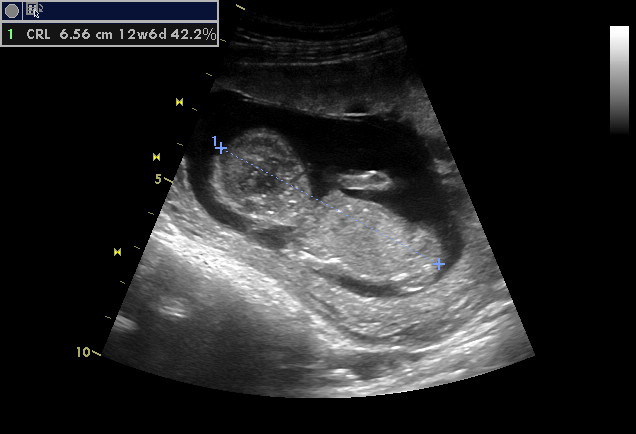

termín 21.12.2012, taky doufám, že to přijde trošku dříve, abychom už byli na vánoce všichni doma... :-) Uvidíme. Jsem taky "stará matka", genetiku chodíme, poslední vyšetření bude po 20. červenci, doufám že vše bude OK, na plodovku se mi opravdu nechce, ale samozřejmě, kdyby bylo nějaké podezření, podstoupila bych to. Přijde mi to takové nepřirozené - takový zásah, ale co se dá dělat, že. Na to jsme měly myslet dříve - my staré matky. Chi. V sobotu ještě jedeme do Chorvatska, doufám, že to bude v poho, velmi nepříjemné období prvních třech měsíců mě opustilo, tak snad mě tak žádná komplikace nepotká. Těším se moc. Přeji krásné těhulkování. A přidávám foto 13+2

[174298]

A teď koukám, že na fotce je 12+6, v papírech má 13+2, tak sama nevím kolik jsem...